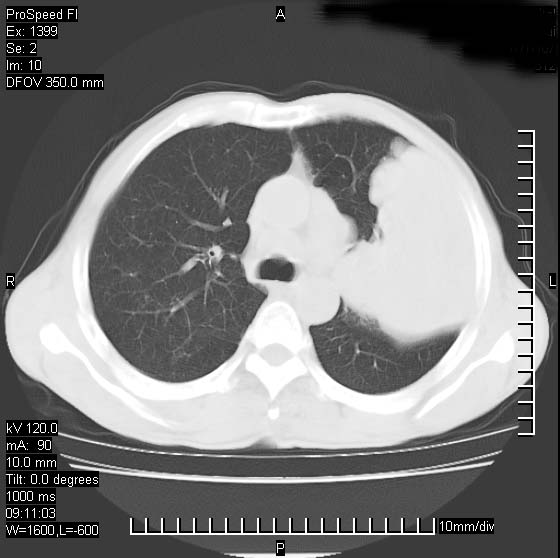

以下是引用卜一在2007-1-19 9:55:00的发言:[br]左肺沿胸膜下巨大肿块影,边缘呈分叶征,纵隔内见肿大淋巴结,右肺内另见一不规则结节影 .考虑:左肺周围性肺癌伴纵隔 右肺内转移.